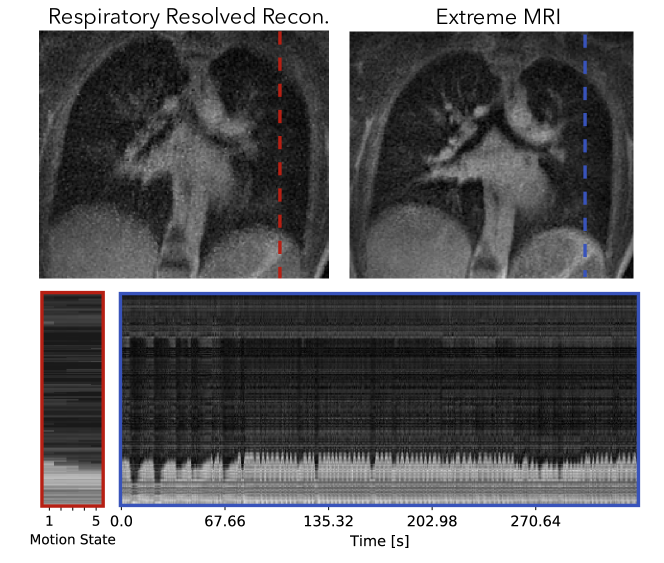

Figure 9 and Supporting Information Video S11 and S12 compare the proposed method with the respiratory-resolved reconstruction. From the cross-section over time and Supporting Information Video S11, regular breathing with slight variable rates can be observed. Overall, Supporting Information Video S11 of the proposed reconstruction shows some temporal flickering artifacts. Looking at each frame individually, the proposed reconstruction shows similar image quality and sharpness as the respiratory resolved reconstruction for the expiration phase. For other phases, the respiratory resolved reconstruction is slightly sharper near the diaphragms.

Refer to caption

Figure 9: Comparison of the proposed method with the respiratory-resolved reconstruction of the first lung dataset. Dynamics can be seen more clearly in Supporting Information Video S11 and S12. From the cross-section over time and Supporting Information Video S11, regular breathing with slight variable rates can be observed. Overall, Supporting Information Video S11 of the proposed reconstruction shows temporal flickering artifacts. Looking at each frame individually, the proposed reconstruction shows similar image quality and sharpness as the respiratory resolved reconstruction for the expiration phase. For other phases, the respiratory resolved reconstruction is slightly sharper near the diaphragms.

4.2.2 Second lung dataset

Figure 10 and Supporting Information Video S13 and S14 compare the proposed method with the respiratory-resolved reconstruction. From the cross-section and Supporting Information Video S13, coughing can be observed in the beginning of the scan for the proposed reconstruction. The patient can be seen to return to a more regular breathing pattern after a while but still occasionally show abrupt motions. The proposed reconstruction does show flickering temporal artifacts when the patient coughs, but in general has less noise-like artifacts and much sharper features than the respiratory resolved reconstruction.